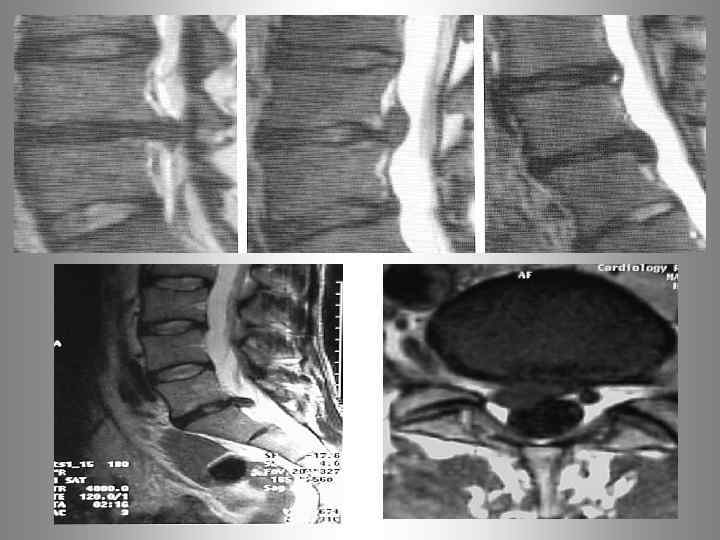

Лучевая диагностика остеохондроза позвоночника. Рентгенография Компьютерная томография (КТ) а) Магнитно-резонансная томография( МРТ) б) МР-миелография Сцинтиграфия Денситометрия В. К. Рентген

Опухоль. Метастаз. Остеопороз. Спондилит (дисцит)

MRT - позвоночника. Спондилит L 2 - L 3 позвонков.